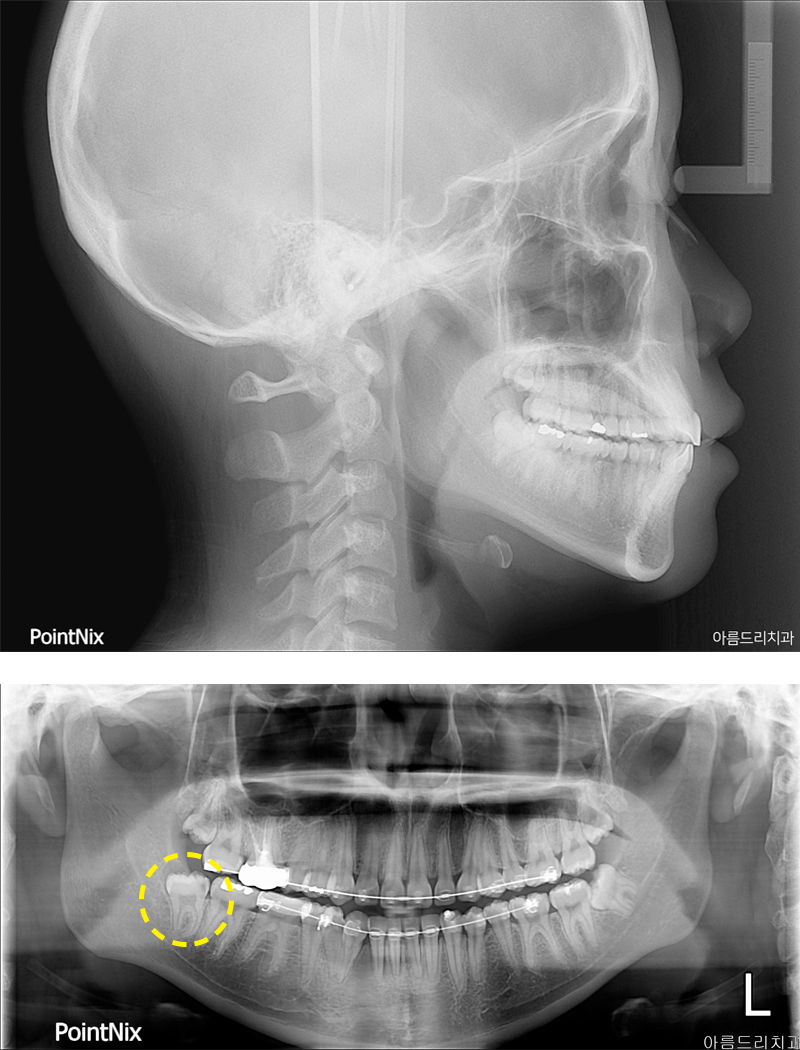

환자분께서는 사랑니 중에서도 난이도가 높은 매복사랑니발치의 케이스였는데요.

매복사랑니란 말그대로 사랑니가 잇몸에 매복 된 상태를 뜻하며 그 각도나 매복된 정도에 따라 다르게 분류되고 치료방법 또한 다르죠.

사진을 보면 우측과 좌측에 매복사랑니가 있는 모습을 확인하실 수 있으실텐데요.

우측에 있는 사랑니와 인접한 치아에 충치가 발생하여 통증이 심해 발치를 원하셨습니다.

파노라마 사진에서도 확인해 보실수 있듯이 매복사랑니발치 케이스인 것을 확인할 수 있었고 육안으로 보기에도 치아가 거의 보이 지 않았으며 더 중요한것은 하악의 사랑니는 설신경과 하치조신경이 지나가기 때문에 매우 신경써서 발치를 진행해야만 합니다.

환자분께서는 얼마 지나지 않아 회사에서 출장 스케쥴이 있으셔서 당일 발치를 원하셨고 아름드리치과의 정밀한 CT촬영과 3차원분석 을 통해 당일 매복사랑니발치를 진행하였어요.